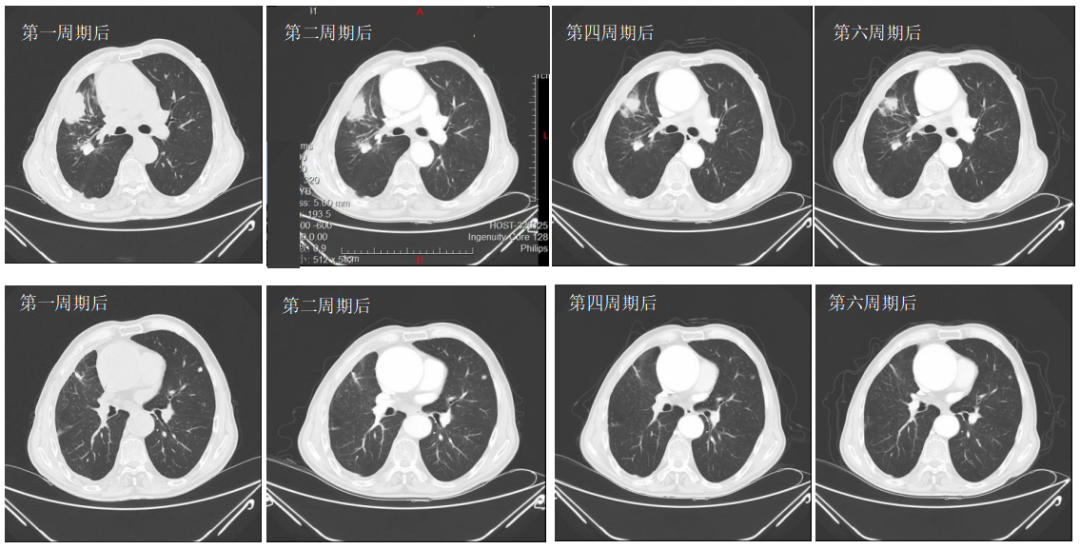

2022-08-15(治疗2周期后)CT、2022-09-28(治疗4周期后)CT、2022-11-08(治疗6周期后)CT:右肺上叶前段软组织密度影逐渐缩小(49mm*27mm→45mm*23mm→44mm*22mm),疗效综合评估SD。